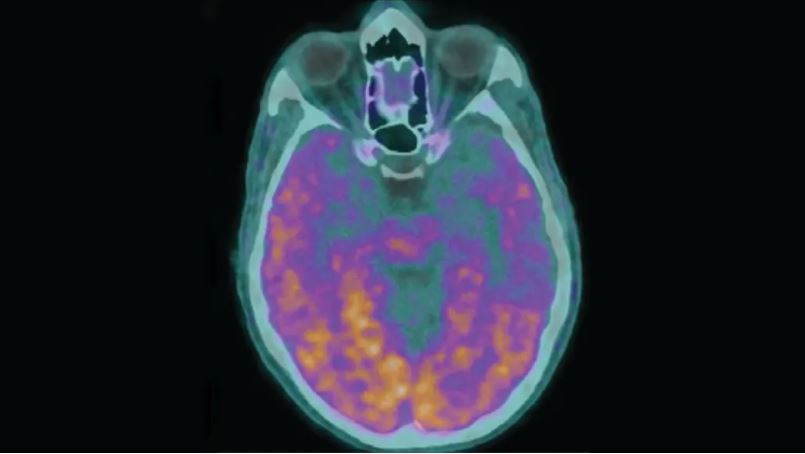

综合ETToday新闻云,美国有线新闻网络(CNN)报道,英国伦敦大学学院朊毒体疾病研究所团队于周一在医学期刊《自然医学》(Nature Medicine)发表研究成果,指出他们发现阿兹海默症的发病途径竟然还包括疑似“人传人”的案例,患者早发性失智症症状,可能是因为β淀粉样蛋白的传播所致,该蛋白在阿兹海默症斑块扮演关键角色。

研究指出,5名成年人患者在童年时期曾经因为缺乏生长激素,而从尸体接收了死者的脑下垂体生长激素,从1959至1985年之间英国至少有1848名患者接收了来自死者脑下垂体的生长激素,美国当时也使用这种治疗手段,然而反复使用多年的生长激素被β淀粉样蛋白污染,可能导致阿兹海默症的传播。

研究发现,从尸体取出的垂体生长激素所产生的污染物中,同时感染了与克雅二氏病有关的朊毒体(Prion)、以及被视为容易诱使阿兹海默症发病的β淀粉样蛋白,也因此在特定情况下,可能造成阿兹海默症传播。